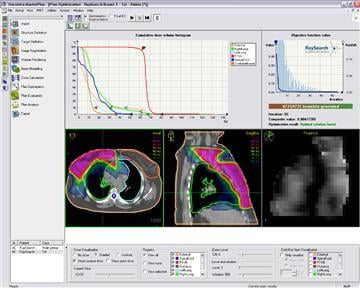

December 11, 2008 - The first patient to be treated clinically with a new treatment planning system for proton radiation therapy developed by RaySearch took place at Uppsala University Hospital in Sweden.

The system is integrated in the Oncentra MasterPlan treatment planning system from RaySearch's partner Nucletron. The University Hospital treats more than 100 cancer patients annually with proton therapy at the The Svedberg Laboratory and the system will be used for all proton treatments in the future.

"The new treatment planning system saves substantial time with its user-friendly tools providing us with various optimization alternatives and the possibilities of making fine adjustments. The dose calculations are exact and optimized to the clinical reality. In addition to the concise presentation of treatment plan data, filter and field shapes are visualized graphically in a clear and pleasant manner," said Christina Vallhagen Dahlgren, senior hospital physicist, proton therapy at the University Hospital.